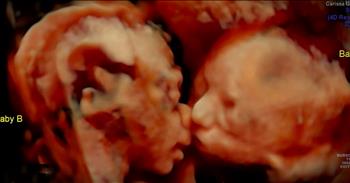

Mom-To-Be Sees Twins Kiss In Ultrasound

Carissa Gill had seen her twin baby girls before through ultrasound. But when she went in for one check up they saw something beyond beautiful. Carissa's baby girls were giving each other kisses! When you see the photos your heart will be so full. What incredible little miracles.